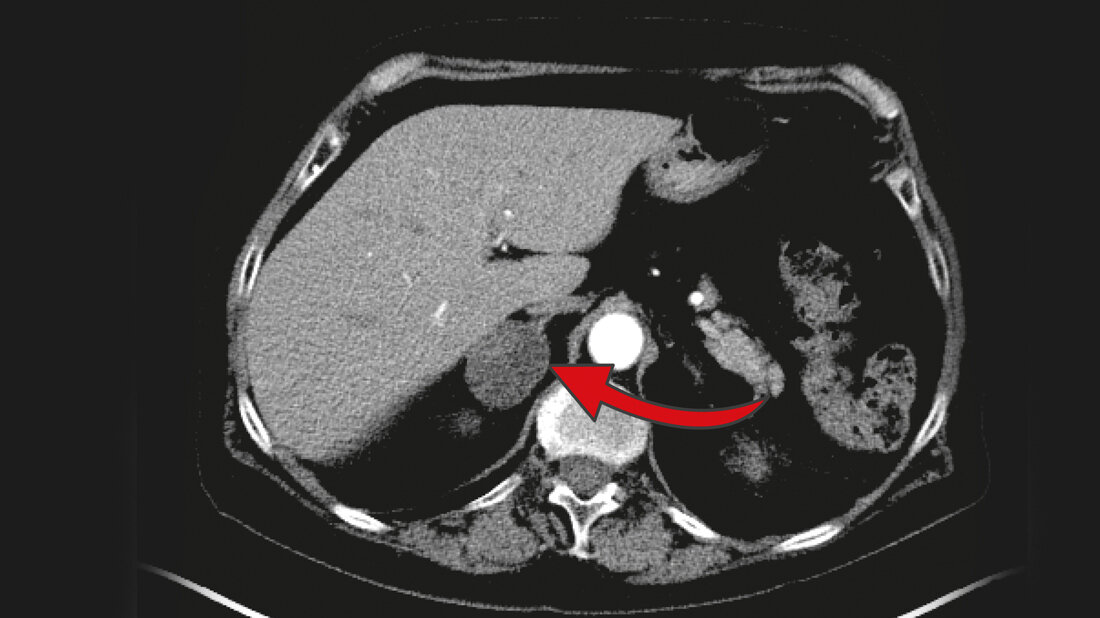

Nebennierentumoren gehören laut Deutscher Gesellschaft für Endokrinologie zu den häufigsten Tumoren beim Menschen überhaupt. Drei Prozent der über 50-Jährigen haben Nebennierentumore. Bei den über 80-Jährigen ist sogar jeder zehnte betroffen. 80 bis 90 Prozent dieser Tumore, die meist zufällig, zum Beispiel bei einer Computertomografie bei Gallenproblemen, Nierensteinen oder Rückenleiden, entdeckt werden, sind jedoch gutartig und vermeintlich harmlos. Vermeintlich deshalb, weil eine leicht gesteigerte Produktion des Hormons Kortisol, die viele dieser Tumore mit sich bringen, vor einiger Zeit die Meinungen spaltete: Muss man den Tumor operativ entfernen oder nicht?